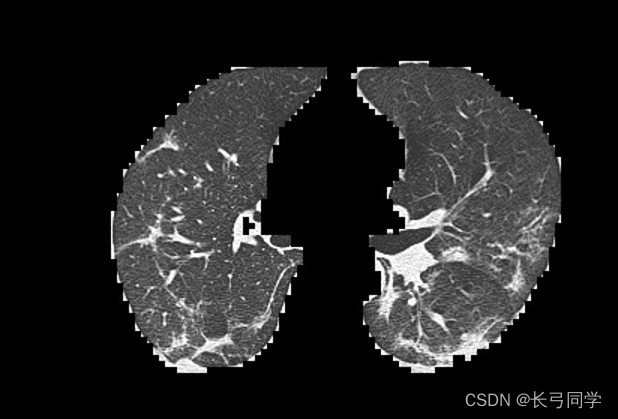

1. COVID-19肺炎肺部CT图特征简述

主要为间质化改变,磨玻璃影